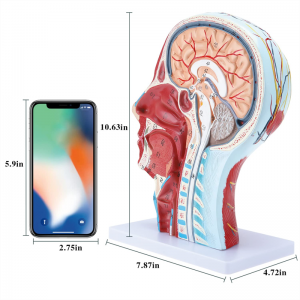

| Nama produk | Tengkorak manusia dengan model neurovaskular otot |

| Bahan | PVC |

| Dimensi | 21*12*27cm |

| Ciri -ciri | Model ini menunjukkan morfologi tempatan bahagian dalam dan luar bahagian median sagittal kepala dan leher, serta struktur saluran darah dan saraf, dan terdapat 84 bahagian yang menunjukkan tanda -tanda secara keseluruhan. |

【1: 1 LifeSize】 Seksyen Median 1: 1 Model otot vaskular neural yang besar dan leher besar (sebelah kanan). Pengerjaan yang baik. Menawarkan pelbagai ciri anatomi.

【Model anatomi otak yang berkualiti tinggi, diperbuat daripada bahan PVC yang mesra alam, mudah dibersihkan. Model anatomi dicat tangan dan dipasang dengan perhatian yang paling terperinci.

【Model otot neurovaskular cetek】 Sangat terperinci, nombor yang ditandai, telinga boleh dilepaskan, memperdalam pemahaman otot, kapal, saraf dan struktur dalaman kepala & leher. Red-artery, biru-vein, kuning-saraf.

【Ciri -ciri】 Ia menunjukkan otot -otot cetek muka yang terdedah; saluran darah cetek & saraf muka & kulit kepala; struktur dalaman kelenjar parotid & saluran pernafasan atas; Struktur keratan rentas sagittal tulang belakang serviks.

【Aplikasi】 Model ini adalah pilihan pertama untuk pejabat doktor, sekolah, hosipital dan clincs. Benar -benar bantuan pengajaran yang hebat untuk kursus anatomi & fisiologi, demonstrasi, alat komunikasi untuk doktor dan pesakit.

Model ini menunjukkan butiran leher kepala kanan dan bahagian pertengahan sagittal manusia. termasuk cetek

otot muka yang terdedah; saluran darah dangkal dan saraf muka dan kulit kepala; struktur dalaman

kelenjar parotid dan saluran pernafasan atas; Struktur keratan rentas sagittal tulang belakang serviks.

Model ini menunjukkan morfologi tempatan bahagian sagittal medial dan lateral kepala dan leher dan struktur vaskular dan sarafnya, dengan jumlah 100 petunjuk tapak.

Model ini adalah model otot neurovaskular yang besar dan leher yang besar, 1 komponen, menunjukkan butiran kepala kanan dan leher manusia dan bahagian sagittal median, termasuk otot -otot dangkal yang terdedah pada muka, kapal cetek muka dan skalp, saraf, saraf, saraf, saraf, saraf, saraf, saraf, saraf, saraf, saraf, saraf, saraf, saraf, saraf, saraf, saraf, saraf, saraf, saraf, saraf, saraf, saraf, saraf, saraf, saraf, saraf, saraf, saraf, saraf, saraf, saraf, saraf, saraf, saraf, saraf, dan struktur medial kelenjar parotid dan saluran pernafasan atas, dan struktur bahagian sagittal tulang belakang serviks